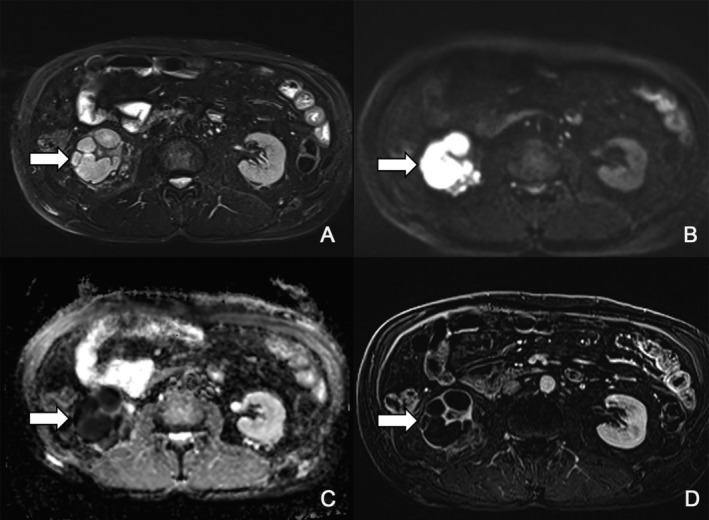

Crizotinib, an anaplastic lymphoma kinase (ALK)/ROS1/c-MET inhibitor, improves outcomes in ALK-positive non-small cell lung cancer (NSCLC) but can cause crizotinib-associated renal cysts (CARCs), a rare yet clinically relevant adverse effect. We report a case of a 68-year-old Korean male who developed complex renal cysts after 4 years of crizotinib therapy. Radiologic findings initially raised suspicion for either an abscess or a neoplastic lesion, leading to surgical resection. However, recurrent renal cysts developed during continued crizotinib therapy, and CARCs were subsequently suspected. A dose reduction was implemented, which led to cyst regression without compromising tumor control. This case highlights the need to recognize and manage late-onset toxicities during long-term treatment, emphasizing the clinical value of multidisciplinary evaluation and tailored dose adjustments.

克唑替尼是一种间变性淋巴瘤激酶(ALK)/ROS1/c-MET抑制剂,可改善ALK阳性非小细胞肺癌(NSCLC)的预后,但可引起克唑替尼相关肾囊肿(CARCs),这是一种罕见但临床相关的不良反应。我们报告一例68岁的韩国男性谁发展复杂的肾囊肿后4年的克唑替尼治疗。放射学结果最初怀疑为脓肿或肿瘤病变,导致手术切除。然而,在继续克唑替尼治疗期间,复发性肾囊肿出现,随后怀疑为CARCs。减少剂量,导致囊肿消退而不影响肿瘤控制。该病例强调了在长期治疗过程中识别和管理迟发性毒性的必要性,强调了多学科评估和量身定制剂量调整的临床价值。